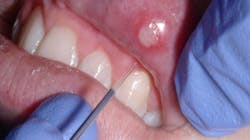

Using lasers to arrest herpetic lesions is one of the best practice builders we can have. Of course, the best time to treat a herpetic lesion is from its onset, but that doesn’t always work within our patients’ schedules. I may see my patient at any stage of the lesion: from the time the patient feels tissue tightness and discomfort, to the time the lesion blisters and ulcerates, or as it heals. By placing laser energy into these lesions, discomfort is eliminated almost instantly, allowing the area to heal quickly. Typically, instead of the area taking 10-14 days to resolve, it typically heals in three to five days.

To treat these areas, I start with a very low laser power setting of .3W and hover about 2 mm over the lesion. I move the laser in a cross-hatching motion over the lesion without touching it. Move the laser energy horizontally and then vertically to cover the entire area. I follow with a power setting of .5W, moving on to .7W, and then finishing up with .9W and 1.0W. Use a cross-hatching movement in all these instances.

The length of time needed to treat herpetic lesions will depend on the size of area. For example, a small lesion may only take 20 seconds per setting, whereas a larger area may need 60 seconds per setting.

Remember that you aren’t lasering off the lesion itself; it will look the same as it did when you started the procedure since you’re only arresting the area. However, healing will begin immediately. To complete the procedure, I place vitamin E over the lesion.

Inform your patient that herpetic lesions are extremely contagious and that they must make sure not to touch the area. Tell them to take care when applying lipstick, lip gloss, and makeup so they don’t spread the lesion to other areas.

When using the laser on an aphthous ulcer, the settings are the same. The pain from the ulcer will be eliminated, and the area will heal quickly.